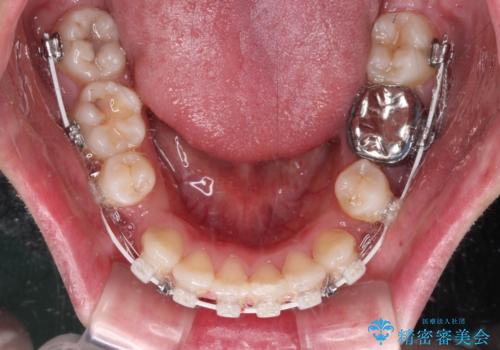

口ゴボが気になる 上下4本の抜歯矯正

- 前歯のデコボコやクロスバイト、口元の突出感を気にして来院された患者様です。

上下左右の第一小臼歯4本を抜歯して、ワイヤー装置にて矯正治療を行うこととしました。

途中出産や育児があり、治療期間長くなってしまいましたが、ストレスなく唇が閉じられるような口元に仕上げることができました。